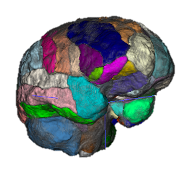

Quantitative Volumetry

Measuring the volume and appearance of brain and spinal cord structures can yield important insights about the health of the underlying tissue. Abnormal shrinkage of certain brain areas early in the course of multiple sclerosis (MS) can herald clinical decline. For example, the thalamus is one of the earliest structures to shrink in MS and we collaborate with the Saranathan Lab in assessing thalamic subnuclear segmentation. We employ a wide variety of tools to accurately quantify brain structures. Among many, these can include Freesurfer, FSL, SPM, C3D, ITK-SNAP, 3D Slicer, and ANTs. We are now implementing newer deep learning segmentation tools that can be trained on relatively small datasets as well. The Principal Investigator (PI) runs a longitudinal, observational study of MS (the OPTIMUM study) to study real-world information from persons with MS, a resource that allows new insights into the disease by combining MRI with clinical data informatics.